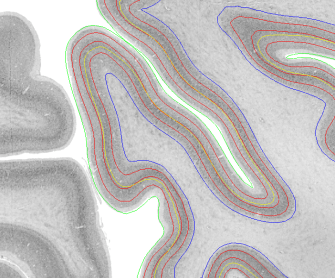

Description: Collection of tools for surface-based operations developed from Konrad Wagstyl, Casey Paquola, Richard Bethlehem, Alan C Evans, and Alexander Huth written in python.

It can use Freesurfer surfaces and to estimate equi-distant and equi-volume surfaces across the cortical depth.

Code and instructions: https://github.com/kwagstyl/surface_tools